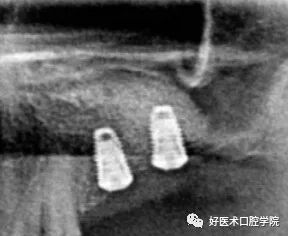

(4)通过上颌窦外提升手术摘除囊肿后同期或择期种植

北京大学口腔医学院·口腔医院口腔种植中心对X线影像学确诊患上颌窦囊肿的32例患者共33侧囊肿先行口内上颌窦外侧壁入路,摘除部分上颌窦囊肿壁,使其开放后自行萎缩,关闭口腔黏膜入路;3~6个月后二次入路行上颌窦底提升植骨术,同期或延期植入种植体,共植入62枚种植体。患者随访平均(30.9±11.5)个月(12~56个月),随访期间3枚种植体因骨结合失败脱落,种植体的存留率为95%(59/62),随访期间未见囊肿复发。

2015年文献报道了12例患者通过颊侧附加窗口取出囊肿,保证了上颌窦提升区黏膜完整性,术后7例同期植入,5例择期植入,术后回访无复发,植体稳定。